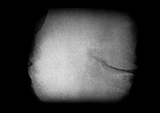

まず問診や触診を行った上で、関節のすき間や変形などの状態を調べるレントゲン(X線)検査が行われます。このとき診断によく使われるのが、変形性ひざ関節症の重症度を示すグレードという指標。グレードは1から4までに分けられており、2以降が変形性ひざ関節症と診断される基準です。グレード2が初期、3が進行期、4が末期と対応しており、進行に伴って関節の隙間が狭くなったり、骨が大きくとがる骨棘(こつきょく)ができたりします。

Kellgren-Lawrence分類(K-L分類)

ひざ関節の隙間が75%以下となり、消失することもある。大きな骨棘が形成され、骨の変形も顕著に認められる、末期の段階。